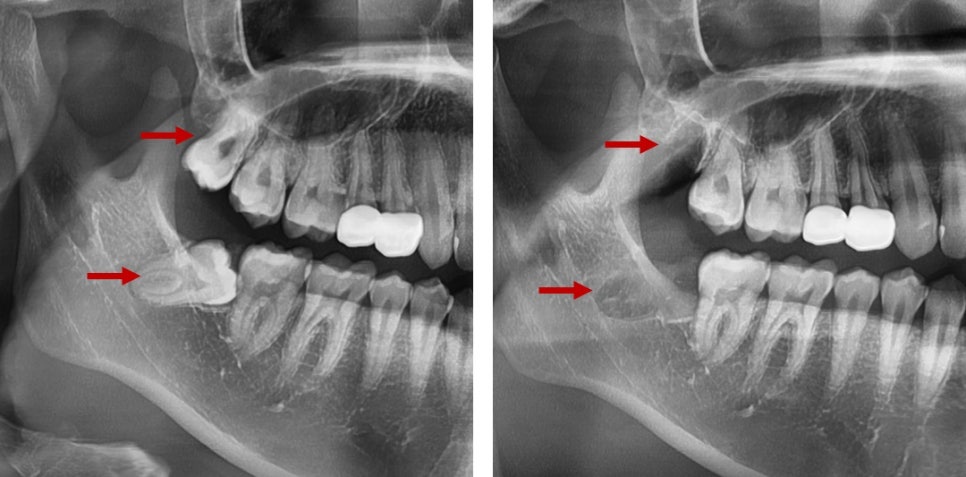

위 그림과 같이 주변 치아에 문제를 주거나

염증이나 낭종 또는 통증을 유발할 때는 발치를 추천드리고 있습니다